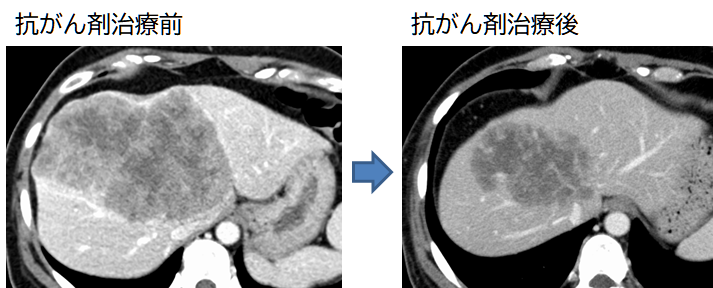

肝転移を有する大腸・直腸がんや、神経内分泌腫瘍の患者さんでは、転移個数が多いため、あるいは転移腫瘍が大きいために当初、手術が不可能と診断されることがあります。このような場合には全身化学療法を行いますが、近年の抗がん剤の進歩や分子標的薬の登場により、内科的治療中に腫瘍が劇的に小さくなったり見えなくなったりして、手術が可能となることがしばしばあります。このような患者さんについては術前画像シミュレーションを行った上で(リンク)、多数の転移を残らず切除するようにしています。